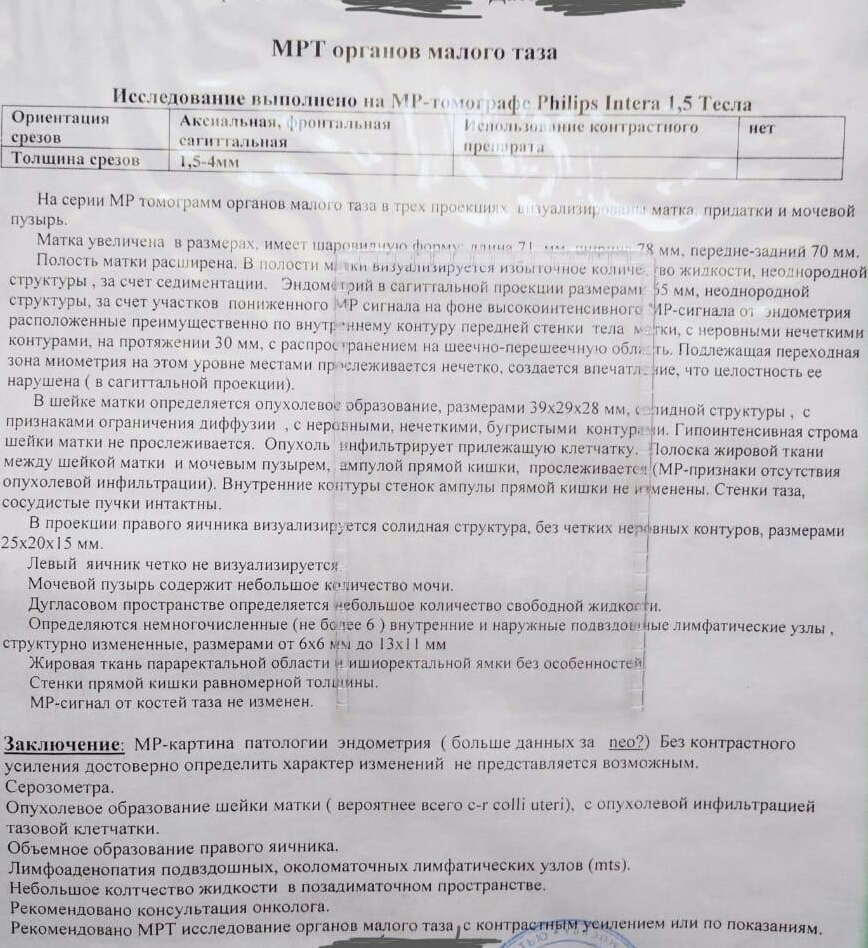

Компьютерная томография органов малого таза: оборудование и результаты исследований